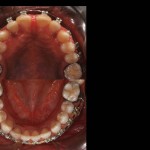

Foto e documentazione